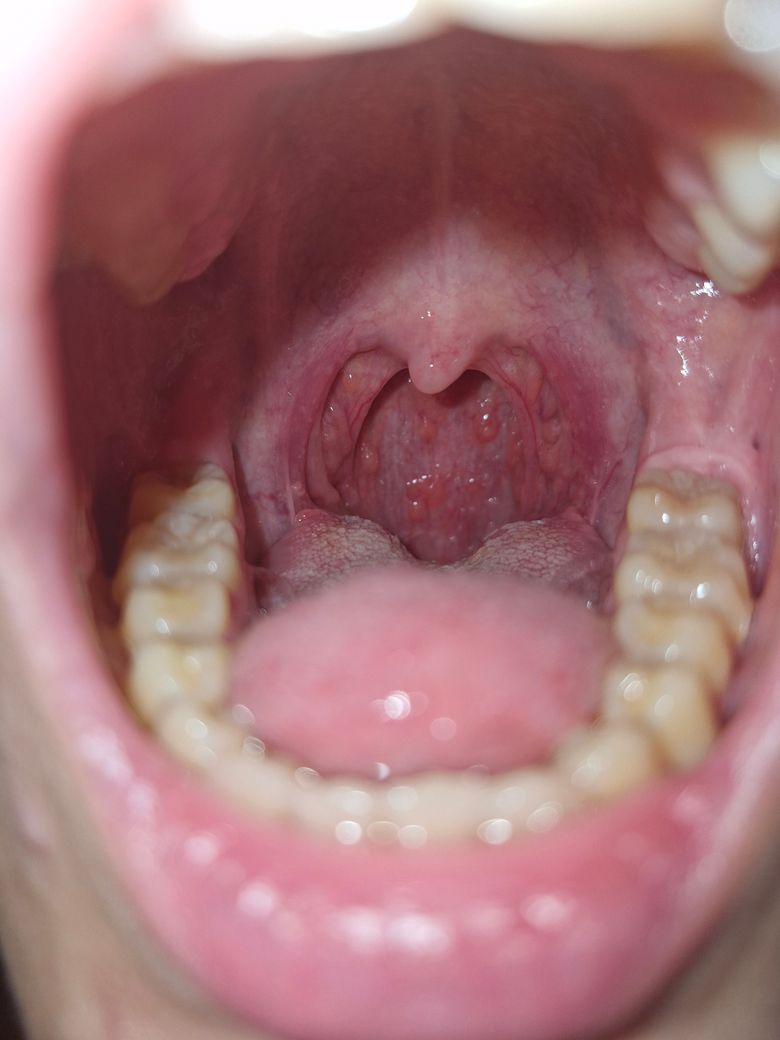

목구멍 뾰루지가 있는데 병원을 가봐야할까요?

안녕하세요. 증상은 몇주 됐는데요. 초반에 인후통 조금 있다가 눈물샘쪽과 비강쪽의 통증이 있었습니다. 각각 안과와 이비인후과에서 약 처방을 받으니 증상은 사라졌구요. 물론 그때에도 목구멍 뾰루지는 있었던 것 같습니다. 근데 이비인후과에서는 목 보시더니 별말 안 하시더라구요.

현재는 9월달이라 비염이 심해져서 자주 콧물이 나오고 목이 간지럽습니다.

오랜만에 노래방에 갔는데 평소보다 고음이 안 올라가서 거울을 확인해보니 뾰루지가 그대로라 질문드려요.

• 안녕하세요. 이송재 이비인후과 전문의입니다.

목은 현재 봤을 때 특이소견은 관찰 되지 않습니다. 인후통 증상이 없다면 굳이 현재는 병원에 내원하여 진료는 안받으셔도 될 것 같습니다.